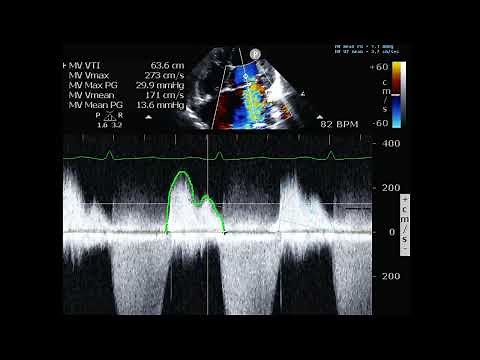

Top suggestions for Quantification of MV Gradient |

Photon Radiation - Mitral Stenosis